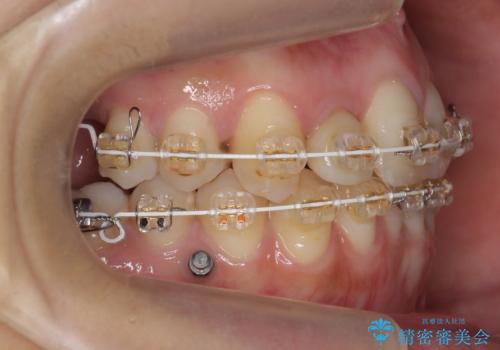

左下の親知らず、左上の小臼歯が残根状態で一本抜いたほかは抜かずに矯正しました。

①保存不可能な歯は抜歯しそのすき間を矯正で閉じる

②右上の親知らずは活かしてブリッジの支台にする

という、予算がかからないように歯を保存する治療計画を立てました。

予算的に右下の一番奥のインプラントは難しかったため、できる限り対応しました。